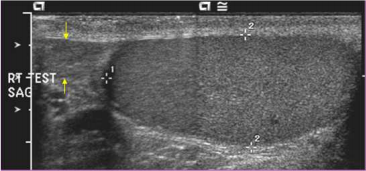

63.右側陰囊掃描如下圖,黃色箭號所指為何? (A)睪丸 (B)副睪丸 (C)睪丸腫瘤 (D)副睪膿瘍